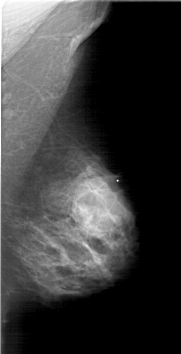

RIGHT_CC LINES 5641 PIXELS_PER_LINE 3061 BITS_PER_PIXEL 12 RESOLUTION 43.5 NON_OVERLAY